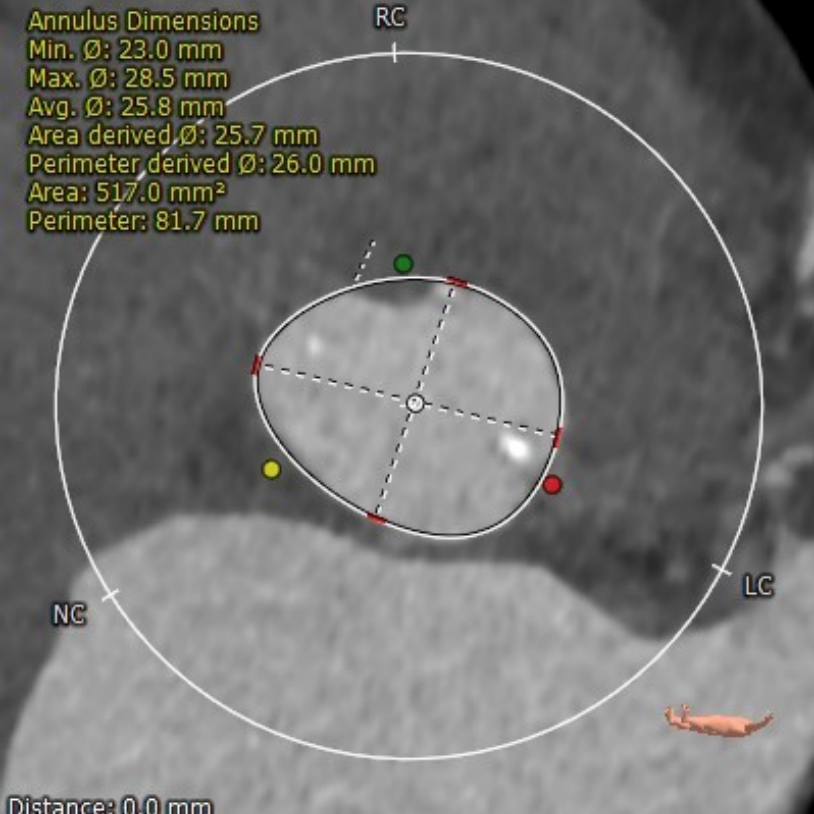

瓣环

周长:68.1mm 平均直径:21.7mm

法氏窦

直径:25.3*24.2*25.1mm

窦管结合部

平均直径:25.8mm

升主动脉

平均直径:31.9mm

左冠高度高度:14.6mm

右冠高度高度:9.8mm

主动脉瓣角度 44°

钙化积分68mm³